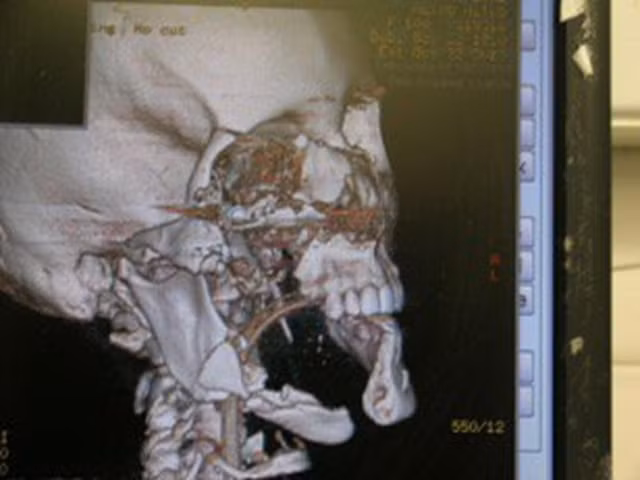

7 năm trước, Christen đến từ bang Virgina, Mỹ đã tự bắn súng vào đầu mình vì “không sợ chết”. Trớ trêu là sau vụ tự tử đó, cô vẫn không chết, chỉ có một nửa khuôn mặt là vĩnh viễn không còn được như xưa: Mất xương hàm phải, 1/3 số răng và lưỡi, 1/4 miệng cùng mắt bên phải.